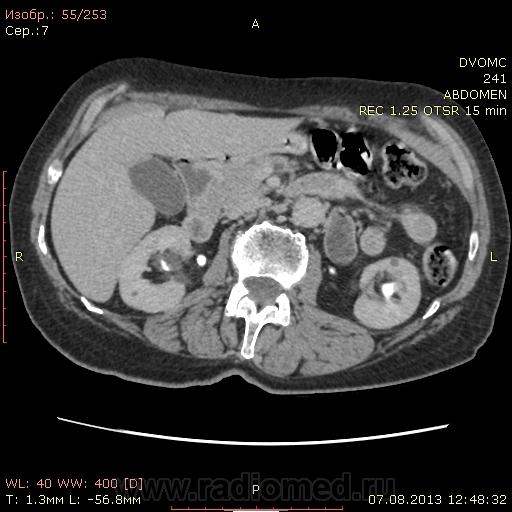

Женщина 73 года. Подскажите, пожалуйста правильно ли я трактую изменения: множественные парапельвикальные и интрапаренхиматозные кисты почек с обеих сторон с деформацией ЧЛС. Перегиб(перетяжка?) желчного пузыря. В остальном - ничего? Еще смутило вот что: контрастное усиление селезенки в артериальной фазе должно быть "пестрым". Всегда до этого пациента было так. Здесь гомогенно усилилась до 135....как это можно расценивать? DICOM файлы http://files.mail.ru/832408BCA4834BBF82010F0764BBDD5A    http://files.mail.ru/422E59E0BACF4E7483F6F9E1FE98ADDF

Да. В большей степени парапельвикальные, чем паренхиматозные.

Билиарный сладж и мелкие конкременты.

Скорее интрапанкреатическая часть холедоха

Похоже на образование правого яичника. Впрочем, в гинекологии предпочтительны УЗИ и МРТ.

Вот, как-то так. Хотя, это может быть и "уехавшая" сюда матка с миоматозным узлом.  Не вижу матки на своем месте. Если удаления не было, возможна она.

Согласна с Андреем Юрьевичем. Только думаю на матку (миома? - УЗИ), а не яичник.